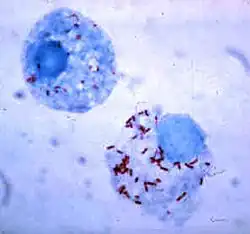

French bacteriologist Charles Nicolle showed in 1909 that lice (Pediculus humanus corporis) were the primary means by which the typhus bacteria (Rickettsia prowazekii) were spread.[1] In his experiments Nicolle infected a chimpanzee with typhus, retrieved the lice from it, and placed them on a healthy chimpanzee who developed the disease shortly thereafter.[2] Further work established that it was lice excrement rather than bites which spread the disease.[2] Nicolle received a Nobel Prize in Physiology and Medicine for his work on typhus in 1928.[2]

After Poland regained its independence, Weigl was hired in 1920 as a professor of biology at the Jan Kazimierz University in Lwów, at the Institute for Study of Typhus and Virology.[3] While there, he developed a vaccine against typhus made from grown lice which were then crushed into a paste. Initially the lice were grown on the blood of guinea pigs but the effectiveness of the vaccine depended on the blood being as similar to human blood as possible. As a consequence, by 1933, Weigl began using human volunteers as feeders. While the volunteers fed healthy lice, there was still the danger of accidental exposure to some of the typhus-carrying lice in the institute. Additionally, once the lice were infected with typhus, they required additional feeding, which carried the risk of the human feeder becoming infected with the disease. Weigl protected the donors by vaccinating them beforehand, and although some of them (including Weigl himself) developed the disease, none died. However, the production of the vaccine was still a potentially dangerous activity, and it was still difficult to produce the vaccine on a large scale.[1][4]

The development of the typhus vaccine involved several stages. First, the lice larvae had to be bred and then fed on human blood. Once they matured, they were removed from the feeders, held down in a clamp machine especially designed by Weigl, and anally injected with the strain of the typhus bacteria. At that point the infected louse had to be fed human blood for about five more days. This stage of the production process carried the greatest risk to the human feeder of contracting the disease. Weigl and his staff tried to prevent the danger by heavily vaccinating the feeders beforehand. Once the louse was sufficiently infected, it was removed from the human feeder, killed in a solution of phenol, and then dissected. The contents of the louse abdomen (its feces) was removed and then ground up into a paste. The paste was then made into the typhus vaccine.[3]

The feeding was done through the use of specially-constructed small wooden boxes, 4 by 7 cm (1+1⁄2 by 2+3⁄4 in), developed by Weigl. The boxes were sealed with paraffin on the top which prevented the lice from escaping, and the underside consisted of a screen made of a fabric sieve, adapted by Weigl from sieves that were used by local peasants to separate wheat husks from the seeds. A typical box contained 400 to 800 lice larvae which would mature as the feeding took place. The sieve bottom allowed the lice to stick out their heads and feed on the human flesh. A standard feeding period took thirty to forty-five minutes, and was repeated with the same lice colony for twelve days. Usually, an individual feeder would accommodate from 7 to 11 boxes (of 400 to 800 lice each) on his or her leg, per feeding session. Typically men would place the boxes on their calves, to minimize the discomfort of the bites, while women feeders placed them on their thighs, so that the bite marks could be covered up by a skirt. A nurse had to watch over the feeding process as the lice would feed beyond the point of being gorged on the blood and could burst if left on the human flesh for too long.[3]